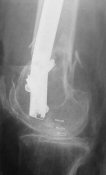

Отправитель: Enes M. Kanlic 13 Ноябрь 2004, 19:43

Dear colleagues,

1. Percutaneous nailing is truly minimally invasive technique, but, unfortunately, nails are not reliable in many hands.

Attached are few examples from our Hospital:

A. Difficult reductions, even in retrograde nailing (my preference, easier control of "small" distal fragment) and it is much, much harder to do it anterograde (Alex, do you have one good case in your collection of anterograde nailing in very distal fractures - as you have suggested that I

should have done it in my previously posted case?

Malpositioning is much too common (recurvatum, varus - valgus).

B. Fixation loosening: distal cutting of the nail, non-unions do happen (cases attached).

Locking Plating has more distal screws than any nail, fixed angles and provides much better fixation, especially in osteoporotic bone.